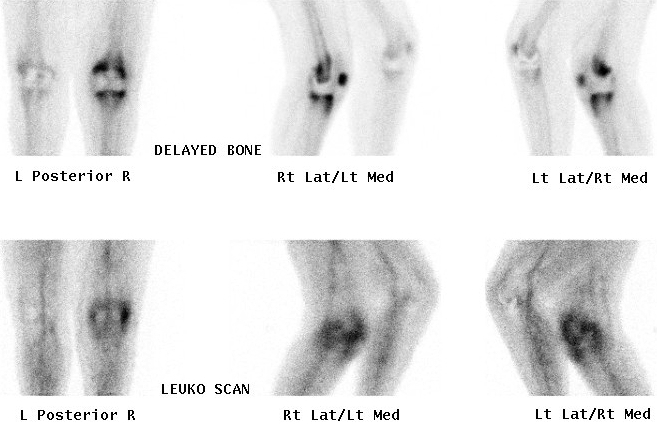

5. Infection

Cellulitis

- Hot flow and pool phases, negative delayed scan

Osteomyelitis

- All 3 phases positive

Technetium or Indium 111-Labelled White cell scan

Technique

Label patients own WBC's with radioactive tracer

Labelled white cells accumulate in areas of inflammation but not in areas of neoplasia

Useful in diagnosing osteomyelitis or infection around joint replacement